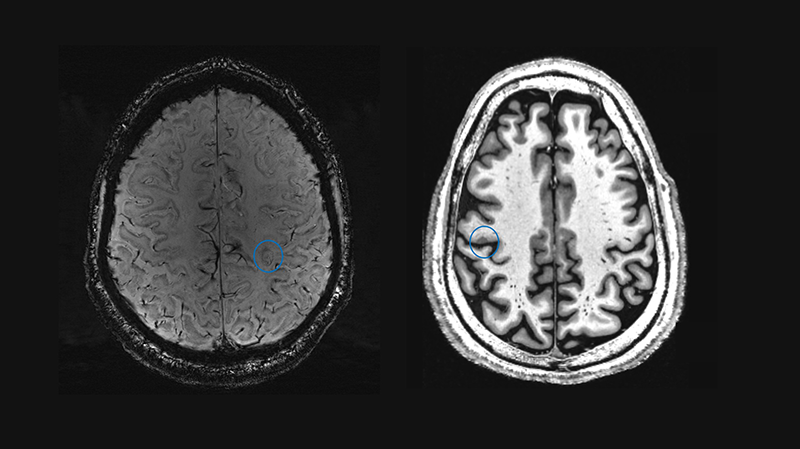

Imaging Biomarkers: paramagnetic rim lesion and central vein sign (left); cortical lesion (right).

Selected publication: 7 Tesla MRI in Multiple Sclerosis: Insights From Its Use in Clinical Routine

Ultra-high-field MRI for improved patient care.

We demonstrated that 7 Tesla ultra-high field MRI can support clinical decision-making in people with suspected multiple sclerosis (MS) when standard imaging does not provide clear answers. In everyday clinical practice, we found that 7 T MRI reveals subtle lesions and specific MS biomarkers that are often difficult to detect with conventional scanners.

By applying 7 T MRI in challenging cases, we were able to clarify diagnoses, increase diagnostic confidence, and in some instances directly influence treatment decisions. This included both confirming MS and ruling it out, helping to choose more appropriate therapies.

Betancourt et al., Eur J Neurol. 2025